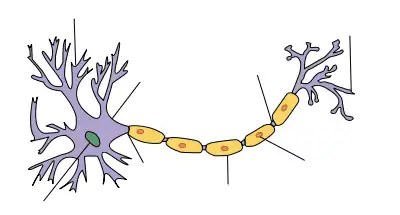

Généralités

La caractéristique pathologique de la maladie est la perte de la gaine de myéline (l'enveloppe graisseuse qui isole et protège les fibres nerveuses) des nerfs périphériques. Un dysfonctionnement du système immunitaire, qui protège normalement le corps contre les agressions externes, produit des anticorps ou des globules blancs (lymphocytes) anormalement dirigés contre la gaine de myéline, entraînant alors un défaut de transmission des informations et ainsi les symptômes de la maladie.

En conséquence, les nerfs touchés ne parviennent pas à répondre à des stimuli, ou ne répondent que faiblement, provoquant des engourdissements, des picotements, des douleurs, une faiblesse musculaire progressive, une perte des réflexes tendineux (aréflexie), de la fatigue et des sensations anormales.